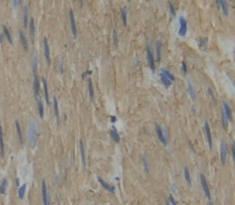

The antibody is a rabbit polyclonal antibody raised against MYH3. It has been selected for its ability to recognize MYH3 in immunohistochemical staining and western blotting.

Immunohistochemistry: 5-20µg/mL;